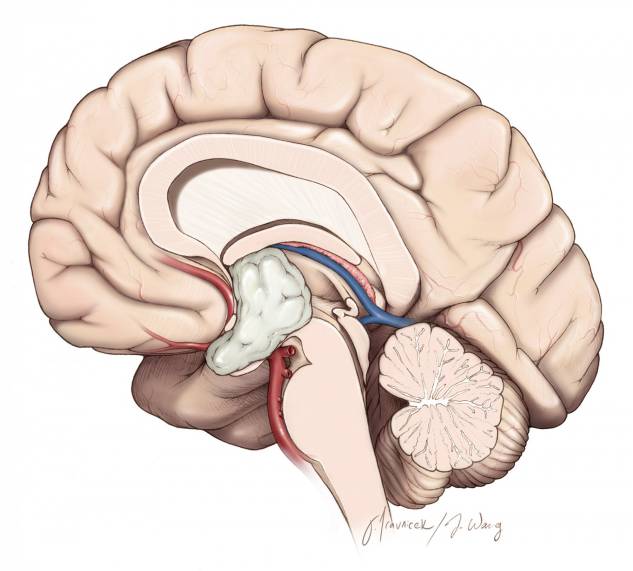

本章关注的特定区域是三脑室的前部,它大约位于视交叉和Monro 孔之间的部分空间。其边界包括视交叉、终板、前联合和穹隆柱。

图3. 图示三脑室前部的解剖通道。脑室的大小、因肿瘤所致的室间孔和前脉络裂扩大的程度决定半球间手术通道的侧别。